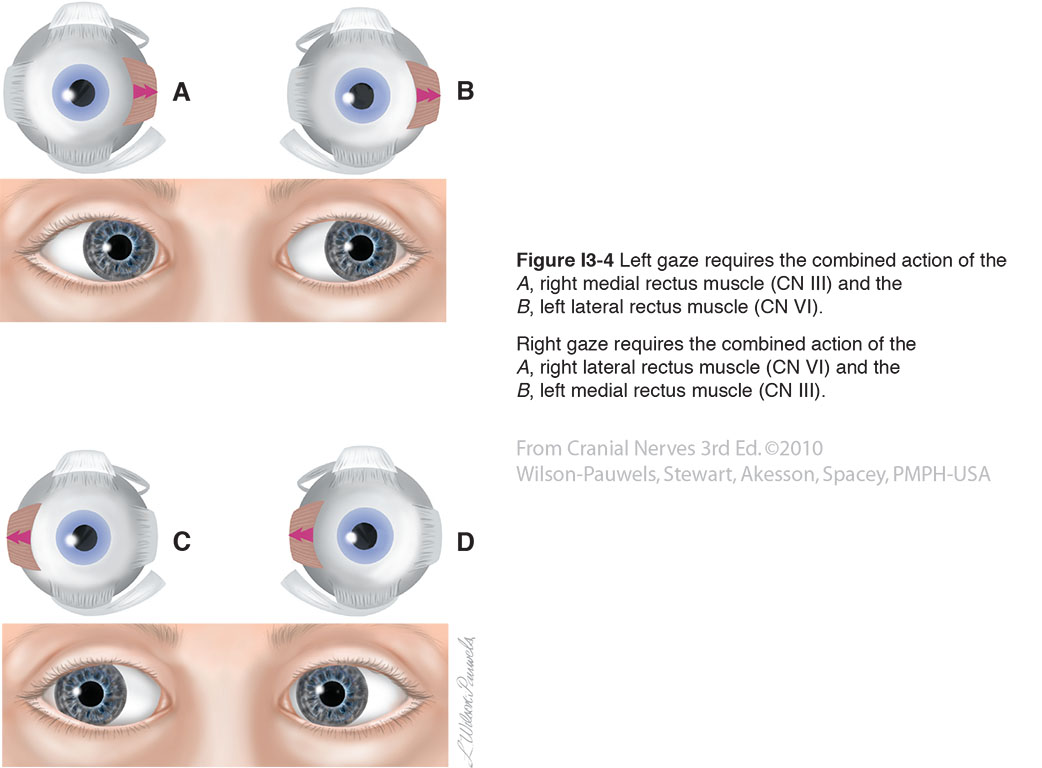

Cranial Nerves 3rd Edition: Eye Movements

bmc.utm.utoronto.ca

bmc.utm.utoronto.ca

movements oblique inferior rectus cranial nerves medial

Cranial Nerves 3rd Edition: Eye Movements

bmc.utm.utoronto.ca

bmc.utm.utoronto.ca

cranial nerves rectus lateral medial movements